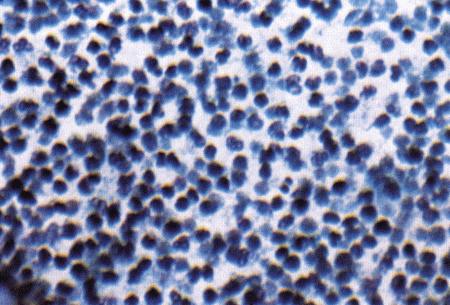

Вагинальная цитология

Повышение концентрации эстрадиола в период проэструса стимулирует деление клеток в базальных слоях вагинального эпителия, но затем концентрация эстрадиола, а соответственно и эндокринная поддержка образования нового, многослойного эпителия снижается, поэтому в образце обнаруживается больше мертвых ороговевших клеток. По мере развития проэструса снижается количество эпителиальных клеток, содержащих ядро. С начала до середины проэструса в вагинальных мазках обнаруживают повышенное содержание эритроцитов. Пик ороговения совпадает с началом повышения концентрации прогестерона; однако в начале эструса исследование не обнаруживает характерных особенностей, которые могли бы указывать на начало фертильного периода. Как правило, такой период наступает несколькими днями позже (табл. 1.1). Тем не менее вагинальная цитология остается популярным методом определения репродуктивного статуса суки из-за своей дешевизны, простоты и доступности. Для получения образца используют ватный тампон, предпочтительно небольшой, который вводят во влагалище и осторожно берут мазок. Полученные клетки помещают под микроскоп, а затем окрашивают контрастным (трихромом) или неконтрастным (например, препаратом Diff-Quik) веществом. При таком окрашивании мертвые кератинизированные клетки становятся оранжевыми, тогда как активные ядерные клетки, а также базальные и парабазальные эпителиальные клетки приобретают различные оттенки от голубого до зеленого.

Ближе к окончанию эструса вагинальные выделения претерпевают характерные изменения (снова выявляются эпителиальные клетки, содержащие ядро, и появляется большое количество лейкоцитов). Такая картина обычно наблюдается через 7–9 дней после пика ЛГ и известна как «вагинальный мазок метэструса». Изменению характера выделений предшествует переходный период, характеризующийся возрастающим количеством активных клеток и указывающий на окончание фертильного периода и эструса (табл. 1.1).

Вагинальная цитология весьма информативна в плане определения фазы эстрального цикла, однако значительные расхождения во времени появления основных признаков эструса по отношению к пику фертильности ограничивает применение указанной методики.

ВАГИНАЛЬНАЯ ЦИТОЛОГИЯ

Вагинальная цитология отражает гормональные изменения, происходящие в организме кошек (фиг. 2.2), особенно в период течки. Данный метод в племенном разведении кошек применяется реже, чем у собак, поскольку процедура может повлиять на ход цикла.

Во время фазы роста фолликулов в выделениях обнаруживаются поверхностные и кератинизированные клетки, наличие которых объясняется воздействием 17-β-эстрадиола. Процентное содержание безъядерных поверхностных клеток возрастает незначительно. В период фолликулярной фазы основной характеристикой вагинальных выделений является медленное сокращение количества клеток, содержащих ядро, промежуточных и базальных клеток. Однако указанные изменения у кошек менее выражены, чем у сук. Наиболее значимым индикатором активности эстрогена является осветление фона на предметном стекле, связанное с резким сокращением обломков разрушенных клеток и слизи. Содержание эозинофилов заметно ниже, чем у собак, эритроциты отсутствуют.

Фиг. 2.2.

Вагинальные выделения кошки (а). Выделения, типичные для фазы эструса. Большая часть клеток представляет собой безъядерные кератинизированные клетки или клетки с пикнотическим ядром. Присутствуют промежуточные клетки (b). Выделения, характерные для метэструса, — «течки», иногда наблюдаемой у кошек в конце эструса. Присутствуют поверхностные и промежуточные клетки, повышено содержание лейкоцитов. Этот короткий метэструс наблюдается в течение 24–48 часов (см. Приложение)